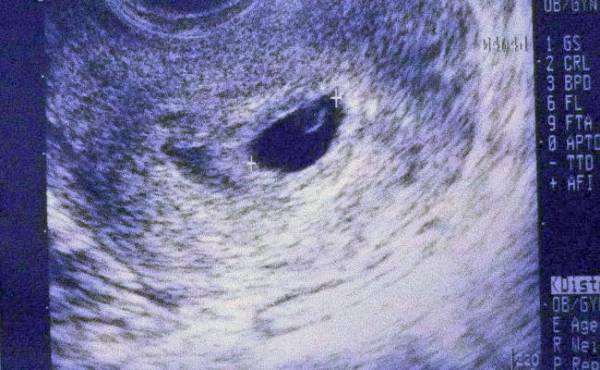

そして妊娠5カ月目に入り、妊娠16週の定期健診で、「ちょっと羊水が多いわね。赤ちゃんも小さめだから、念のため大きな病院に紹介状を書くので早めに明日にでも行ってみて」と言われました。

羊水が多めに見えるのは、胎児の脳の部分に羊水が入り込んでいるためで、そのため胎児の成長も著しく遅く、このまま妊娠を進めても胎内で亡くなる可能性が高いこと、万が一出産できてもすぐに赤ちゃんが亡くなる可能性が高いことを説明されました。